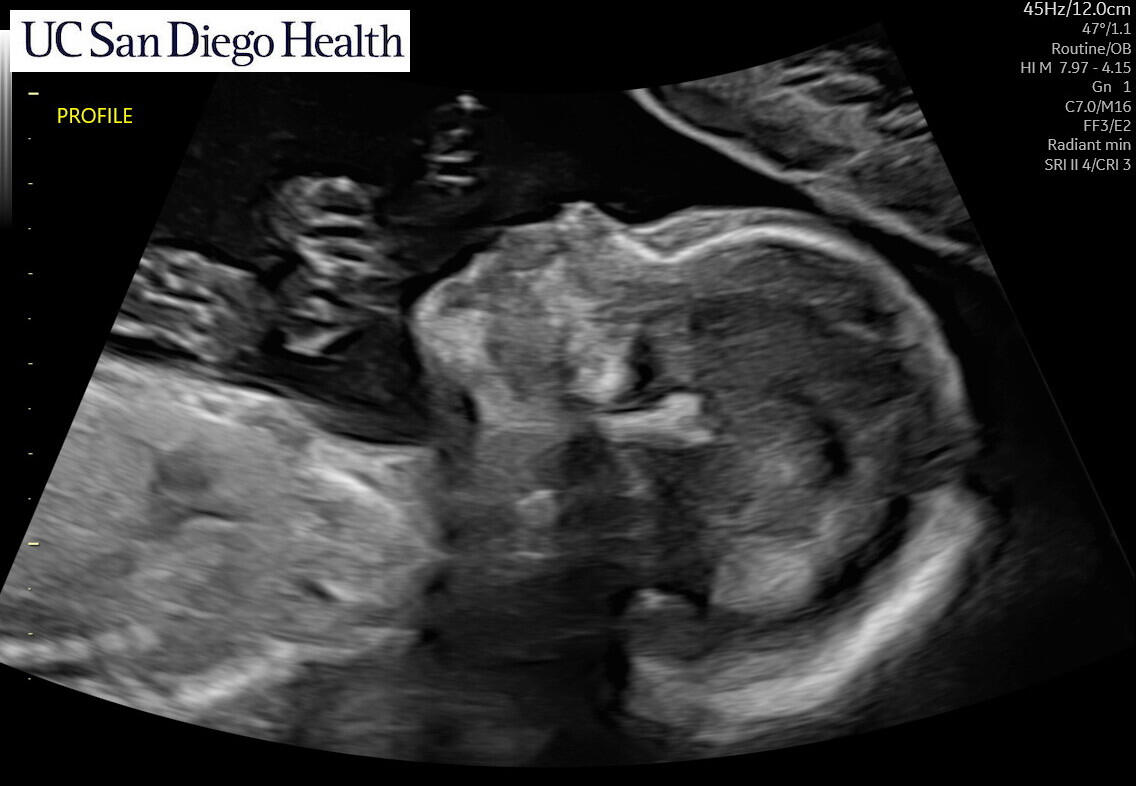

Coming March 2025!

We’re thrilled to be welcoming our baby boy in late March 2025! We’re planning a baby shower in January, we'll see you there!